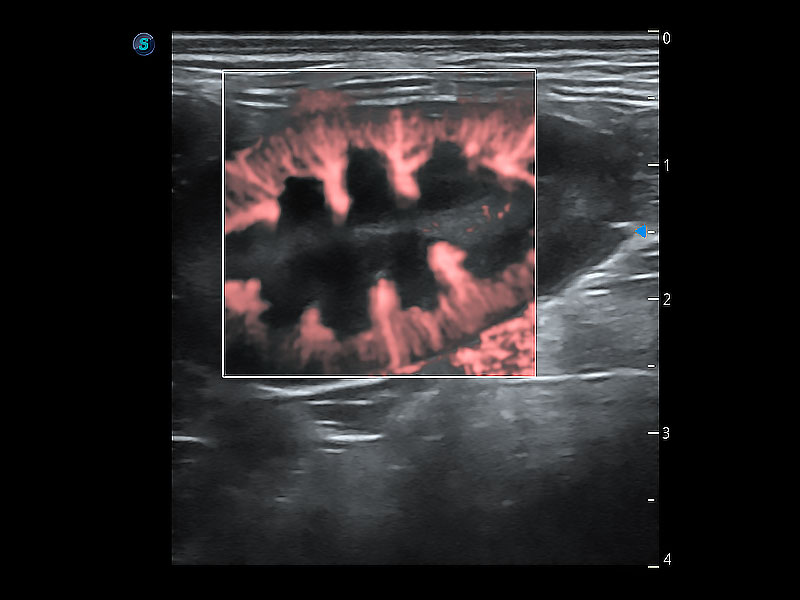

在傳統(tǒng)二維血流成像的基礎(chǔ)上,呈現(xiàn)血流的立體感,具有動感的生命力之美。即便是微小的血管也能輕松應(yīng)對,提高了血流的視覺敏感性。